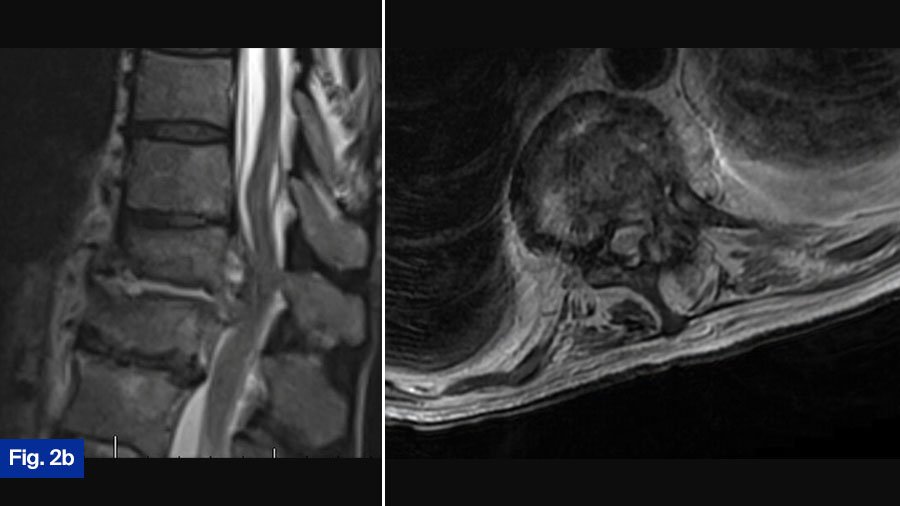

- CT scan: Demonstrated bony destruction and increased segmental kyphosis at T11-T12 (Figure 2a).

- MRI scan: Demonstrated a large ventral epidural phlegmon with moderate cord compression and thoracic hyperintensity with end-plate destruction (Figure 2b).

This patient is the most controversial case. The patient is neurologically intact but has spinal cord compression from an infection. Furthermore, this patient has significant bony erosions. I would treat this patient with surgical intervention in an urgent manner. Significant infection around the spinal cord can cause a spinal cord injury from a mechanical mechanism, but it can also cause vasospasm and spinal infarction. When looking at cervical epidural abscess, Alton et al (TSJ 2015) found a 75% failure rate of medical management largely due to a progressive neurologic deficit. While undoubtably there is some difference between the thoracic and cervical spine, I treat all patients with significant spinal cord compression from an infection surgically. At my institution, this patient would routinely have a lateral partial corpectomy utilizing autologous iliac crest autograft, followed by an instrumented posterior decompression and fusion, The patient would routinely get 6 weeks of IV antibiotics, however the use of suppressive antibiotics after the completion of IV is often variable. While there can be significant debate about the best surgical treatment, I think this patient should undergo surgical intervention.

This case is certainly controversial. At my institution, when such a case is presented at rounds, the room is divided regarding best treatment (initial medical treatment versus initial surgical treatment). Interesting and lively debates occur. This patient presents with a new diagnosis of discitis/osteomyelitis with some bony destruction and epidural abscess. He is neurologically intact and upright radiograph show the segment to be stable. Given this, I would admit the patient and attempt initial medical management. I would monitor response to treatment clinically as well as via laboratory inflammatory markers. Often, in the context of infection that receives adequate medical treatment, we see fusion of the segment. However, this patient will need to be monitored closely once discharged from the hospital with regular clinical assessments with upright radiographs as well as close monitoring by the infectious disease team. It is still possible that this patient requires surgical intervention. Given the growing international academic interest in this disease and the possible growing evidence that initial surgical intervention is best, it is possible that my approach to these types of cases will change as we reach consensus on best treatment.